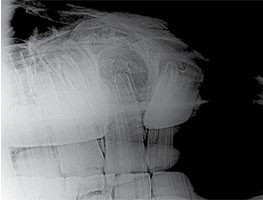

A 3-year-old Quarter horse gelding in good condition had a swelling on his right maxilla that had been increasing in size (Fig. 49). There was nasal discharge with a foul odor coming from the right nostril. The maxilla was swollen in the area of the 107, however the clinical crown looked normal when examined, and there was no mobility of any teeth in the arcade (Fig. 52). There was a small amount of feed packing on the buccal side of the 107. An open mouth lateral oblique radiograph was taken to isolate the enlarged area over the 107 (Fig. 51). Also taken was a dorsal/ventral offset radiograph showing a clear image of the abscess involving the 107 (Fig. 50). It was large and spherical in shape surrounded with dense sclerotic bone. Most root abscesses involving the upper 7’s rupture and drain to the outside of the maxilla. In this case the drain tract was formed into the nasal cavity, which is unusual. This accounts for the purulent nasal discharge coming from the right nostril. The area was surgically prepped, and local anesthesia was infused in the area to desensitize the skin and subcutaneous tissue (Fig. 53). A maxillary nerve block was performed earlier for the oral extraction which lasts approximately 90 to 120 minutes. A skin flap was created first; then the subcutaneous tissue and periosteum were elevated off the bone and transfixed proximally. A 2cm Fortner drill bit was used to make the hole through the maxilla at the proximal end of the abscess. The bone was sclerotic and thick in this area due to the chronic abscess. The hole needs to be big enough to allow a curette to be manipulated in the abscessed area. After debridement of all necrotic tissue and fragments, the periosteum, subcutaneous tissue, and skin were replaced and sutured (Fig. 54). This area should granulate in quickly if all necrotic tissue and fragments have been removed. The communication with the nasal cavity was a small drain tract that was debrided and sutured. The nasal discharge should cease if the drain tract has been resolved. The 107 was extracted orally with the horse standing using sedation and local anesthesia (Fig. 53). This tooth was not difficult to extract because of lack of reserve crown and damaged periodontal attachment. After the tooth was removed, the alveolus was examined for debris and fragments. There were numerous tooth particles about the size of small buckshot laced throughout the necrotic tissue in the abscess.

The abscess was very extensive, making it difficult to curette the infected area, especially the proximal portion from the oral cavity.

We decided to make a small opening through the maxilla to gain access to the infected area for a thorough cleanup of the area. Also, we needed to evaluate the communication of the drain tract to the nasal cavity. Extraction of the 107 without removing the necrotic tissue and tooth fragments may not resolve the infection. Drainage of the abscess is established when the tooth is extracted, but the necrotic tissue and fragments may act as sequestra which will produce a chronic drain tract into the oral cavity. Aggressive debridement of these large abscesses may avoid a second surgery in the future.